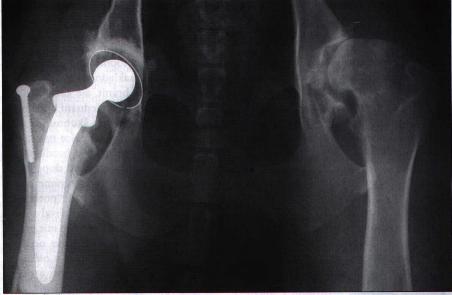

Ostatní operativní zákroky, jako např. trojitá osteotomie pánve, zlepšují mechaniku kloubu (kongruence mezi acetabulem a hlavicí stehenní kosti) a snižuje artrotické změny kyčelního kloubu. Dále můžeme provést tzv. resekci hlavice (pouze u mladých psů do 15kg). Jde o odstranění celé degenerativně změněná kloubní hlavice včetně krčku stehenní kosti. V případě zákroku se musí počítat s lehčím snížením funkčnosti kyčelního kloubu. Ve stadiu příprav (u nás) a finančně náročnější je totální náhrada kyčelního kloubu, která se zpravidla fixuje cementem. V této době je to nejpřijatelnější řešení problémů doprovázejících dysplazii. Její provádění je u nás ale skutečně ojedinělé. Je velice náročné na erudovanost operatéra a sterilitu operačního prostředí. Pro zajímavost v Anglii tato operace vyjde na cca 6700 DM.

Protéza kyčelního kloubu na RTG snímku

Vzhledem k pokročilé artróze tento pes před operací silně kulhal. Po zákroku bylo možno operovanou nohu zase bezbolestně zatěžovat. Později byl úspěšně vyměněn i druhý kyčelní kloub.